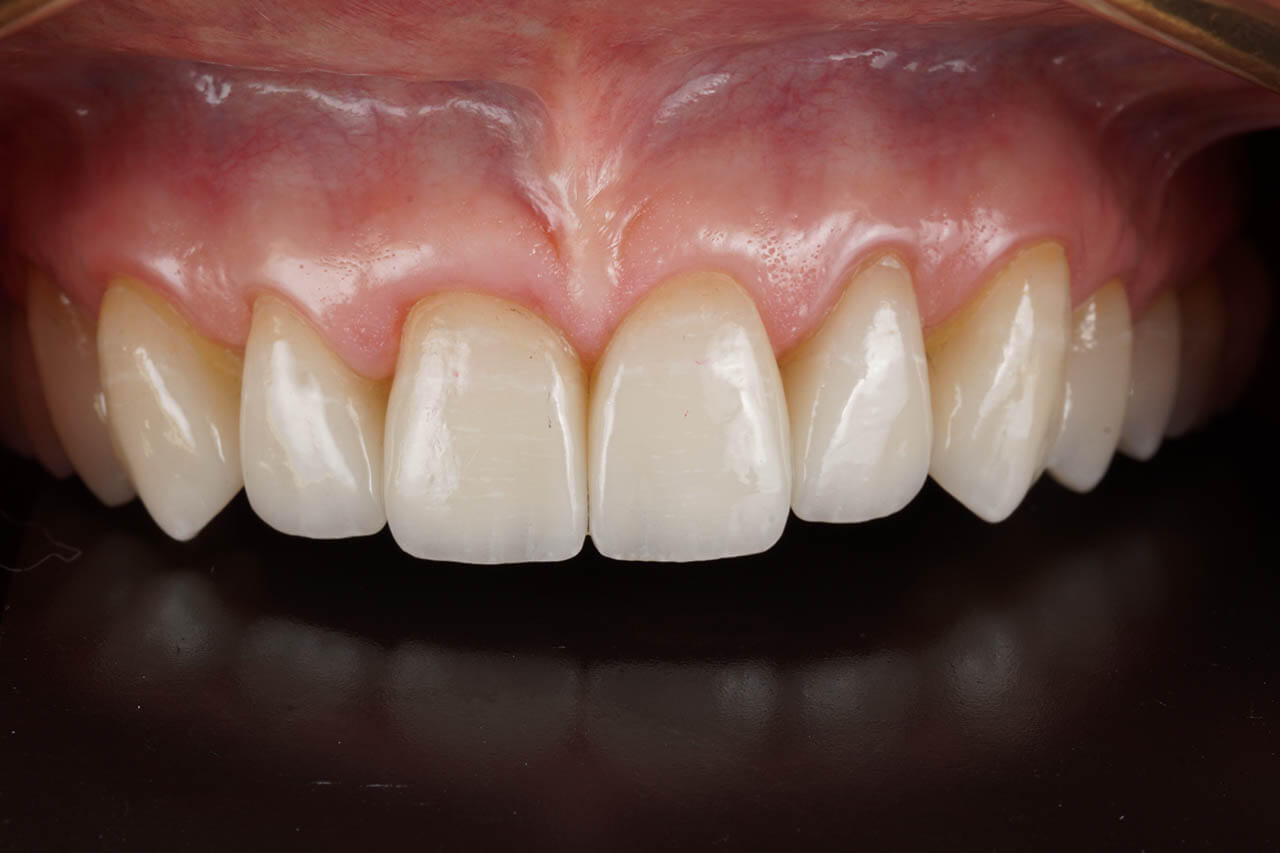

Dental prosthetics deals with filling gaps in the dentition and reconstructing damaged teeth. It is a good choice for anyone who in the past did not properly care for their teeth and as a result could not maintain their natural dentition or lost teeth due to illness or an unfortunate event. A properly chosen partial or full denture allows for the recovery of an aesthetic smile, good well-being, and self-confidence. Prosthetics at the Z Wieży clinic in Władysławowo offers you a wide range of modern prosthetic solutions, from which everyone can choose something tailored to their needs and expectations regarding the final result. Our experienced, highly qualified doctors are ready to provide assistance and good advice. To ensure the highest quality and aesthetics of restorations, we have for years cooperated with a renowned prosthetic laboratory.

Our prosthetic work

CROWNS AND VENEERS

A beautiful, white smile brings more self-confidence and helps achieve success. It can be achieved, among others, through aesthetic medicine treatments or ortholifting.